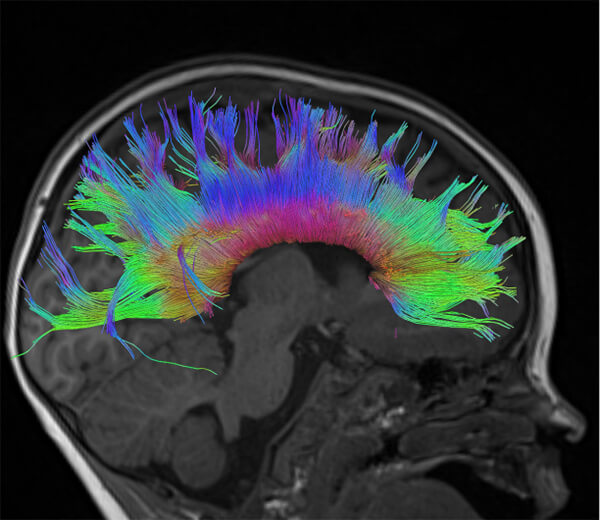

- Special state-of-the-art techniques (fMRI, Multiparametric MRI, Spectroscopy, Tractography, Dynamic Angiography, Neurography, CSF Flow Study)

- Τractography